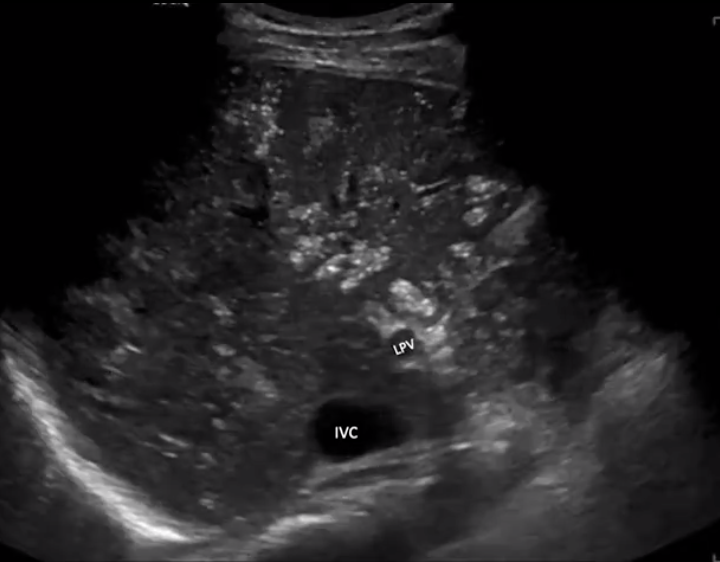

Portal Venous Gas

• Echogenic foci which extend to the periphery of the liver

• Key way to differentiate from pneumobilia which is more centrally located

• Commonly see gas near portal vein

• Bidirectional spikes on doppler (see below)